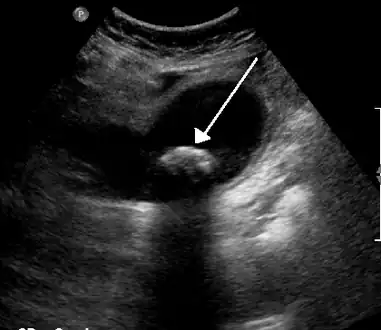

Diagnosis is typically confirmed by abdominal ultrasound. Other imaging techniques used are ERCP and MRCP. Gallstone complications may be detected on blood tests.[2]

On abdominal ultrasound, sinking gallstones usually have posterior acoustic shadowing. In floating gallstones, reverberation echoes (or comet-tail artifact) is seen instead in a clinical condition called adenomyomatosis. Another sign is wall-echo-shadow (WES) triad (or double-arc shadow) which is also characteristic of gallstones.[43]

A 1.9 cm gallstone impacted in the neck of the gallbladder and leading to cholecystitis as seen on ultrasound. There is 4 mm gall bladder wall thickening.